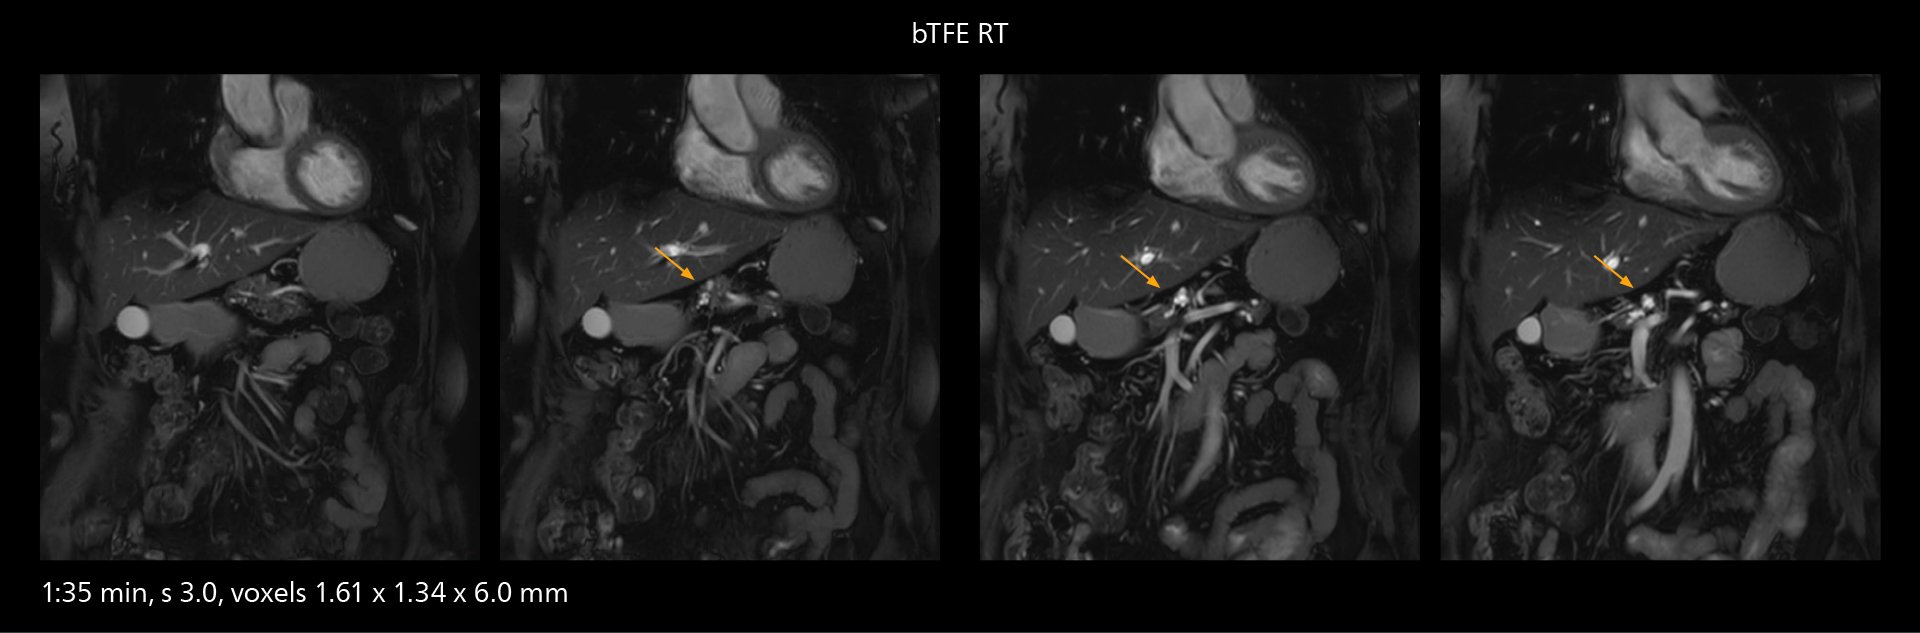

The value of the Elition X gradients is also evident in DWIBS studies. “The fact that we can consistently obtain distortion‐free DWIBS while reducing imaging time at three coronal stations is excellent,” Dr. Makuuchi says. “In these patients, it’s also important that the application of Compressed SENSE to T2‐weighted, STIR and mDIXON sequences has no impact on the examination time of whole‐body imaging. As a result of the increased speed and higher image quality we realize, DWIBS studies have now become routine examinations.”

With SmartPath to Elition X the team can obtain excellent quality DWIBS imaging and reduce imaging time. Other sequences also fit in the examination slot. This case shows left paravertebral neurogenic tumor and Th10 vertebral hemangiomas.